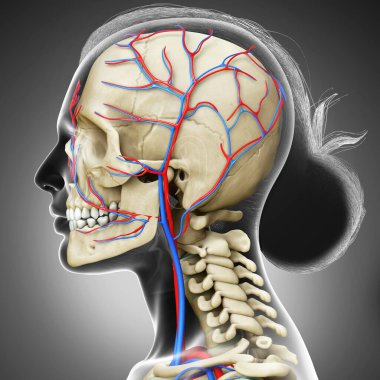

iskelet adam yan görünüm baş ve sinir sistemi

resimlemeİnsanSağlıksağlıklıYaşamkanSağlık hizmetleriTıbbiboğazıçizgi filmsemboldişlerKardiyolojikalpnabızgövdeÇizimbiyolojiBilimbölümgemigerçekçiGöğüsorgBilimselanatomidiyagramPompaGergintedavülarterAtriumApexanatomikSinirlerdolaşımaortkoronerventrikülİnsan Vücududamar sistemiPulmoner fizyolojisiFiziksel bölümdolaşımı kanAnatomi gözlerBenzer İçerikler